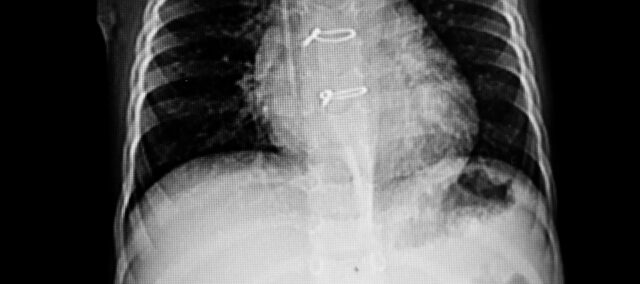

Первичным результатом было разделение грудины, измеренное с помощью ультразвука. Расстояние между двумя половинами грудины определялось количественно, и отмечалась точка наибольшего разделения. В качестве вторичного результата использовалась шкала нестабильности грудины, которая оценивает целостность грудины от 0 баллов (клинически стабильная грудина) до 3 баллов (значительное движение или расслоение). Измерения были получены на исходном уровне (7-й день после операции) и на 4-й неделе.

В исследование были включены 36 женщин, у которых острая нестабильность грудины была подтверждена ультразвуком. Исходные характеристики показали две сопоставимые группы. У них было исходное расхождение грудины 0,23 см.

Первичный результат - расхождение грудины на 4-й неделе - составил 0,13 см в экспериментальной группе и 0,22 в контрольной. Это дало межгрупповую разницу в -0,09 см (95% ДИ от 0,07 до 0,11) в пользу группы вмешательства, выполняющей упражнения для стабилизации туловища после стернотомии.